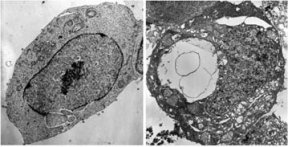

In 1998, Gilloteaux and his colleagues named the process autoschizis, or self-cutting, and published micrographs illustrating it. A new step-by-step, micrographic portrayal of the process appears in this month’s Ultrastructural Pathology.

“I think the pictures are pretty convincing,” says Gilda G. Hillman of Wayne State University’s Karmanos Cancer Center in Detroit. After reading recent papers by Gilloteaux’s group, she says the published descriptions and micrographs definitely illustrate “another cell-death pattern”�one that differs not only from apoptosis but also from the patterns typical of cells killed by radiation.

Throughout much of apoptosis, a cell’s nucleus and its surrounding, watery cytoplasm remain together. Not so in autoschizis. “It’s bizarre, almost as if something told the nucleus and remaining components of affected cells to abandon ship�or in this case, to abandon the cytoplasm,” Gilloteaux says.

In early stages of autoschizis, a crater develops in the cytoplasm as parts of the cell, including the nucleus, congeal and escape the cell membrane. Over the next 4 to 5 hours, the nucleus and other departing structures disintegrate as various enzymes produced by the dying cell snip everything into bits.